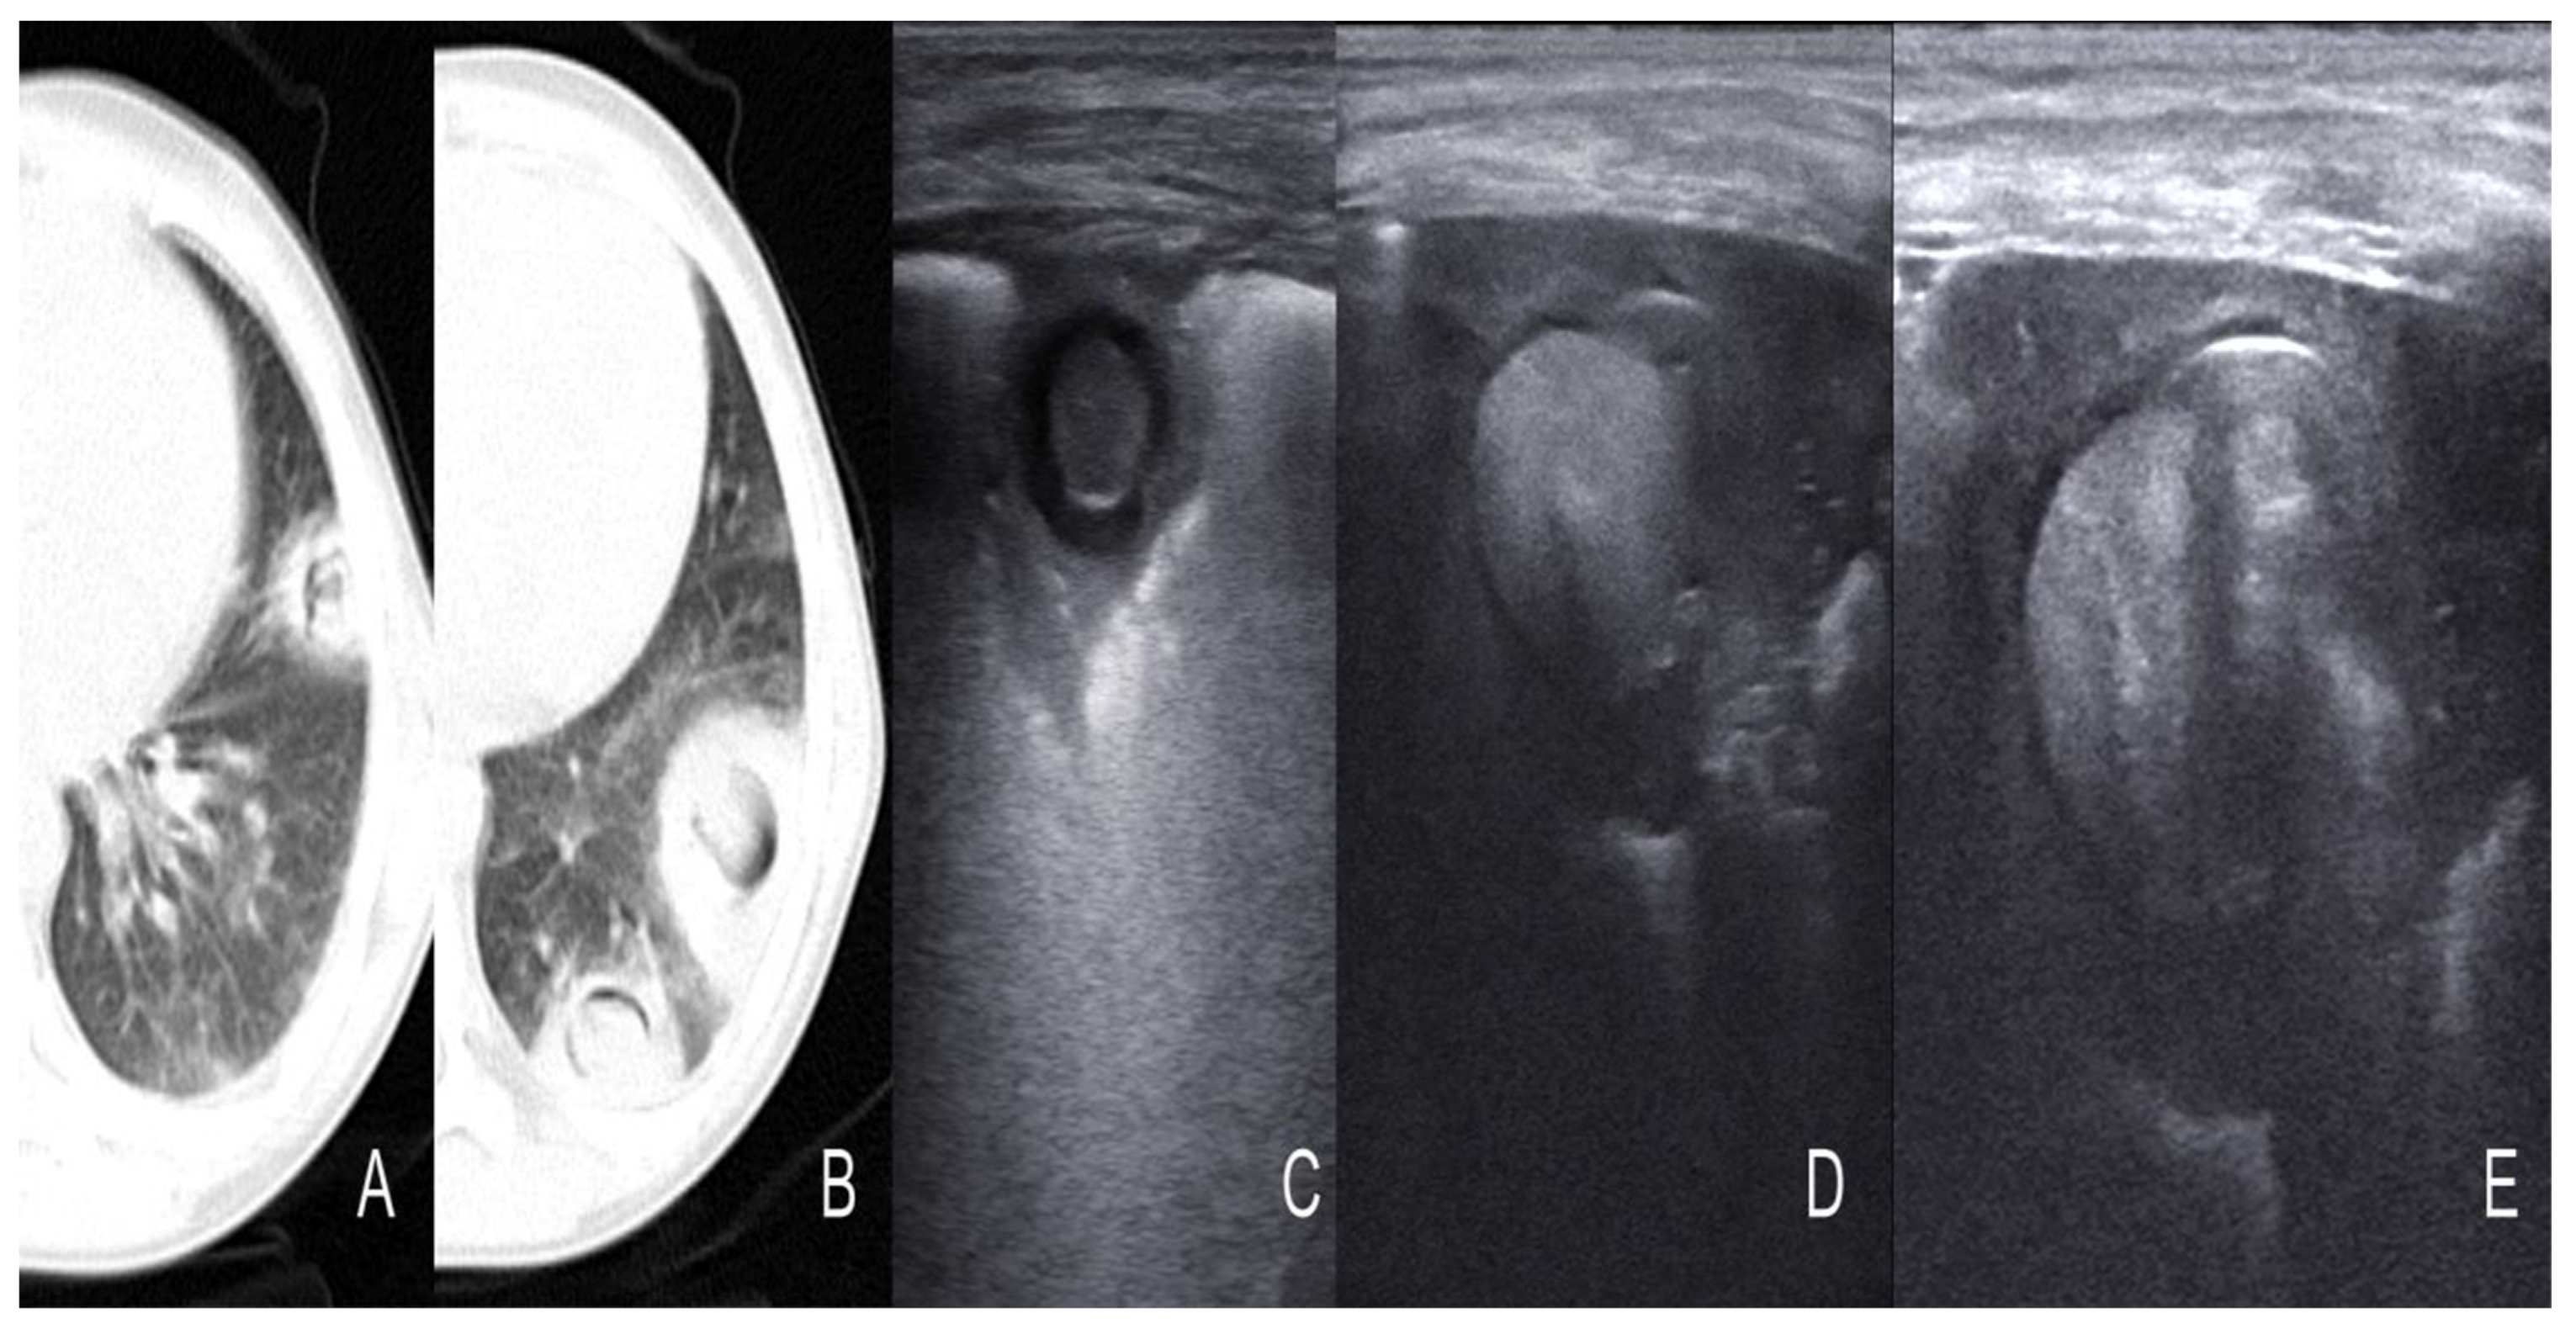

- Trinavarat, P.; Chatchatri, P.; Chandtranuwatana, P. Color Doppler sonography of pulmonary aspergillosis in infants with chronic granulomatous disease. Asian Biomed. 2012, 6, 129–133. [Google Scholar]

- Alamdaran, S.A.; Heidarzadeh, H.; Zavvar, N.; Badlee, Z.; Jaberi, M.; Ghasemi, A. Presentation of Sonographic Features of Pulmonary Invasive Fungal Disease in Six Children with Leukemia. Int. J. Pediatr. 2021, 9, 13203–13211. [Google Scholar] [CrossRef]

- Liu, J.; Ma, H.R.; Fu, W. Lung Ultrasound to Diagnose Pneumonia in Neonates with Fungal Infection. Diagnostics 2022, 12, 1776. [Google Scholar] [CrossRef]